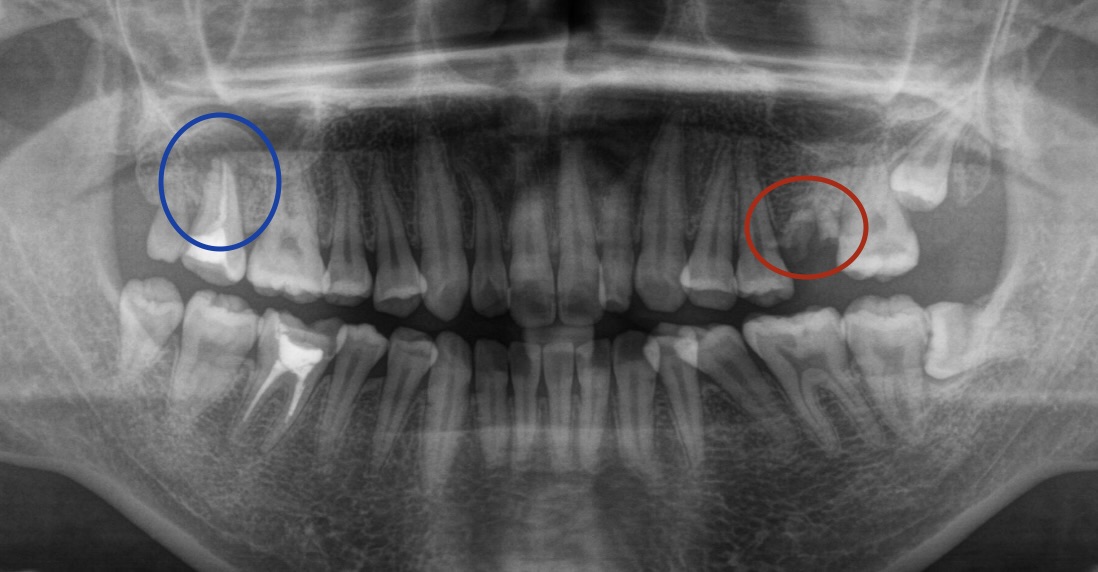

レントゲンを撮影してみると、左上の奥歯はボロボロで根っこだけになっており

(レントゲン画像赤丸部)

右上の奥歯は根っこの先に膿が大きく溜まっているような状態でした。

(レントゲン画像青丸部)